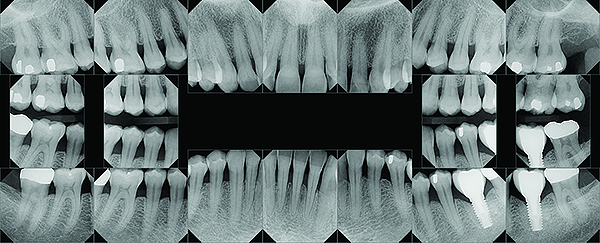

A series of full-mouth diagnostic radiographs that visualize each tooth or implant are critical as a baseline (Figure 11). The frequency and type of radiographs needed at maintenance depends on the severity of periodontal disease, as well as the extent of restorative treatment and caries susceptibility. With more advanced periodontal disease and restorative concerns, more frequent radiographs may be indicated. Vertical bitewing radiographs provide a better view of osseous crest levels and should be considered over horizontal bitewing radiographs for periodontal cases (Figure 12).

Fig 12. Vertical bitewing radiographs.

Figure 12